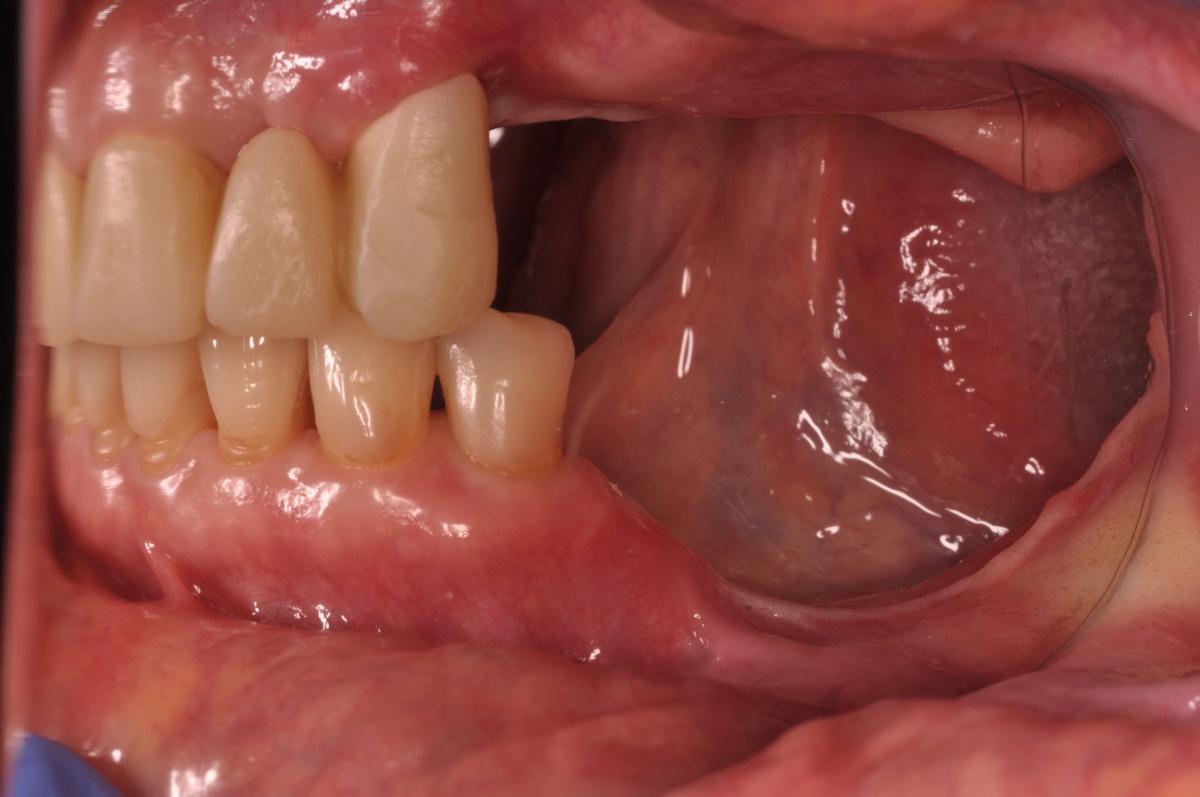

Как выглядит результат спустя несколько лет — на пяти фотографиях ниже

Верхний зубной ряд:

-

Справа. Протяженный мост на 5 единиц с опорой на 3 свои зуба

Передние зубы. Две одиночные коронки + мост на 3 единицы

Слева. 4 коронки с опорой на 4 импланта + зуб мудрости

Нижний зубной ряд:

Справа. Мост на 3 единицы с опорой на 2 импланта + дистопированный зуб мудрости

Передние зубы. 8 собственных +/- живых зубов

Слева. 1 свой зуб под коронкой, 2 коронки с опорой на 2 импланта + дистопированный зуб мудрости